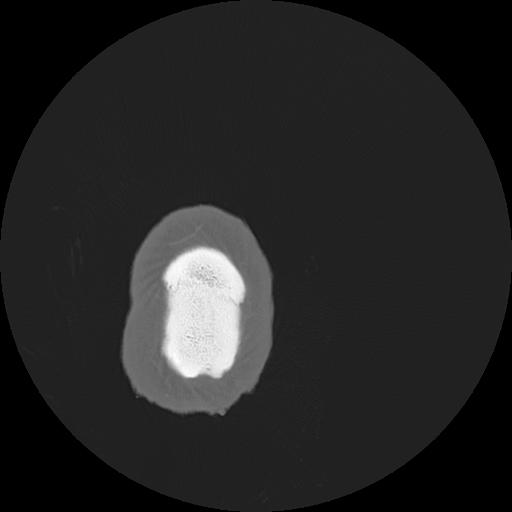

7 HUESO,,Vol,0.5,HUESO,,